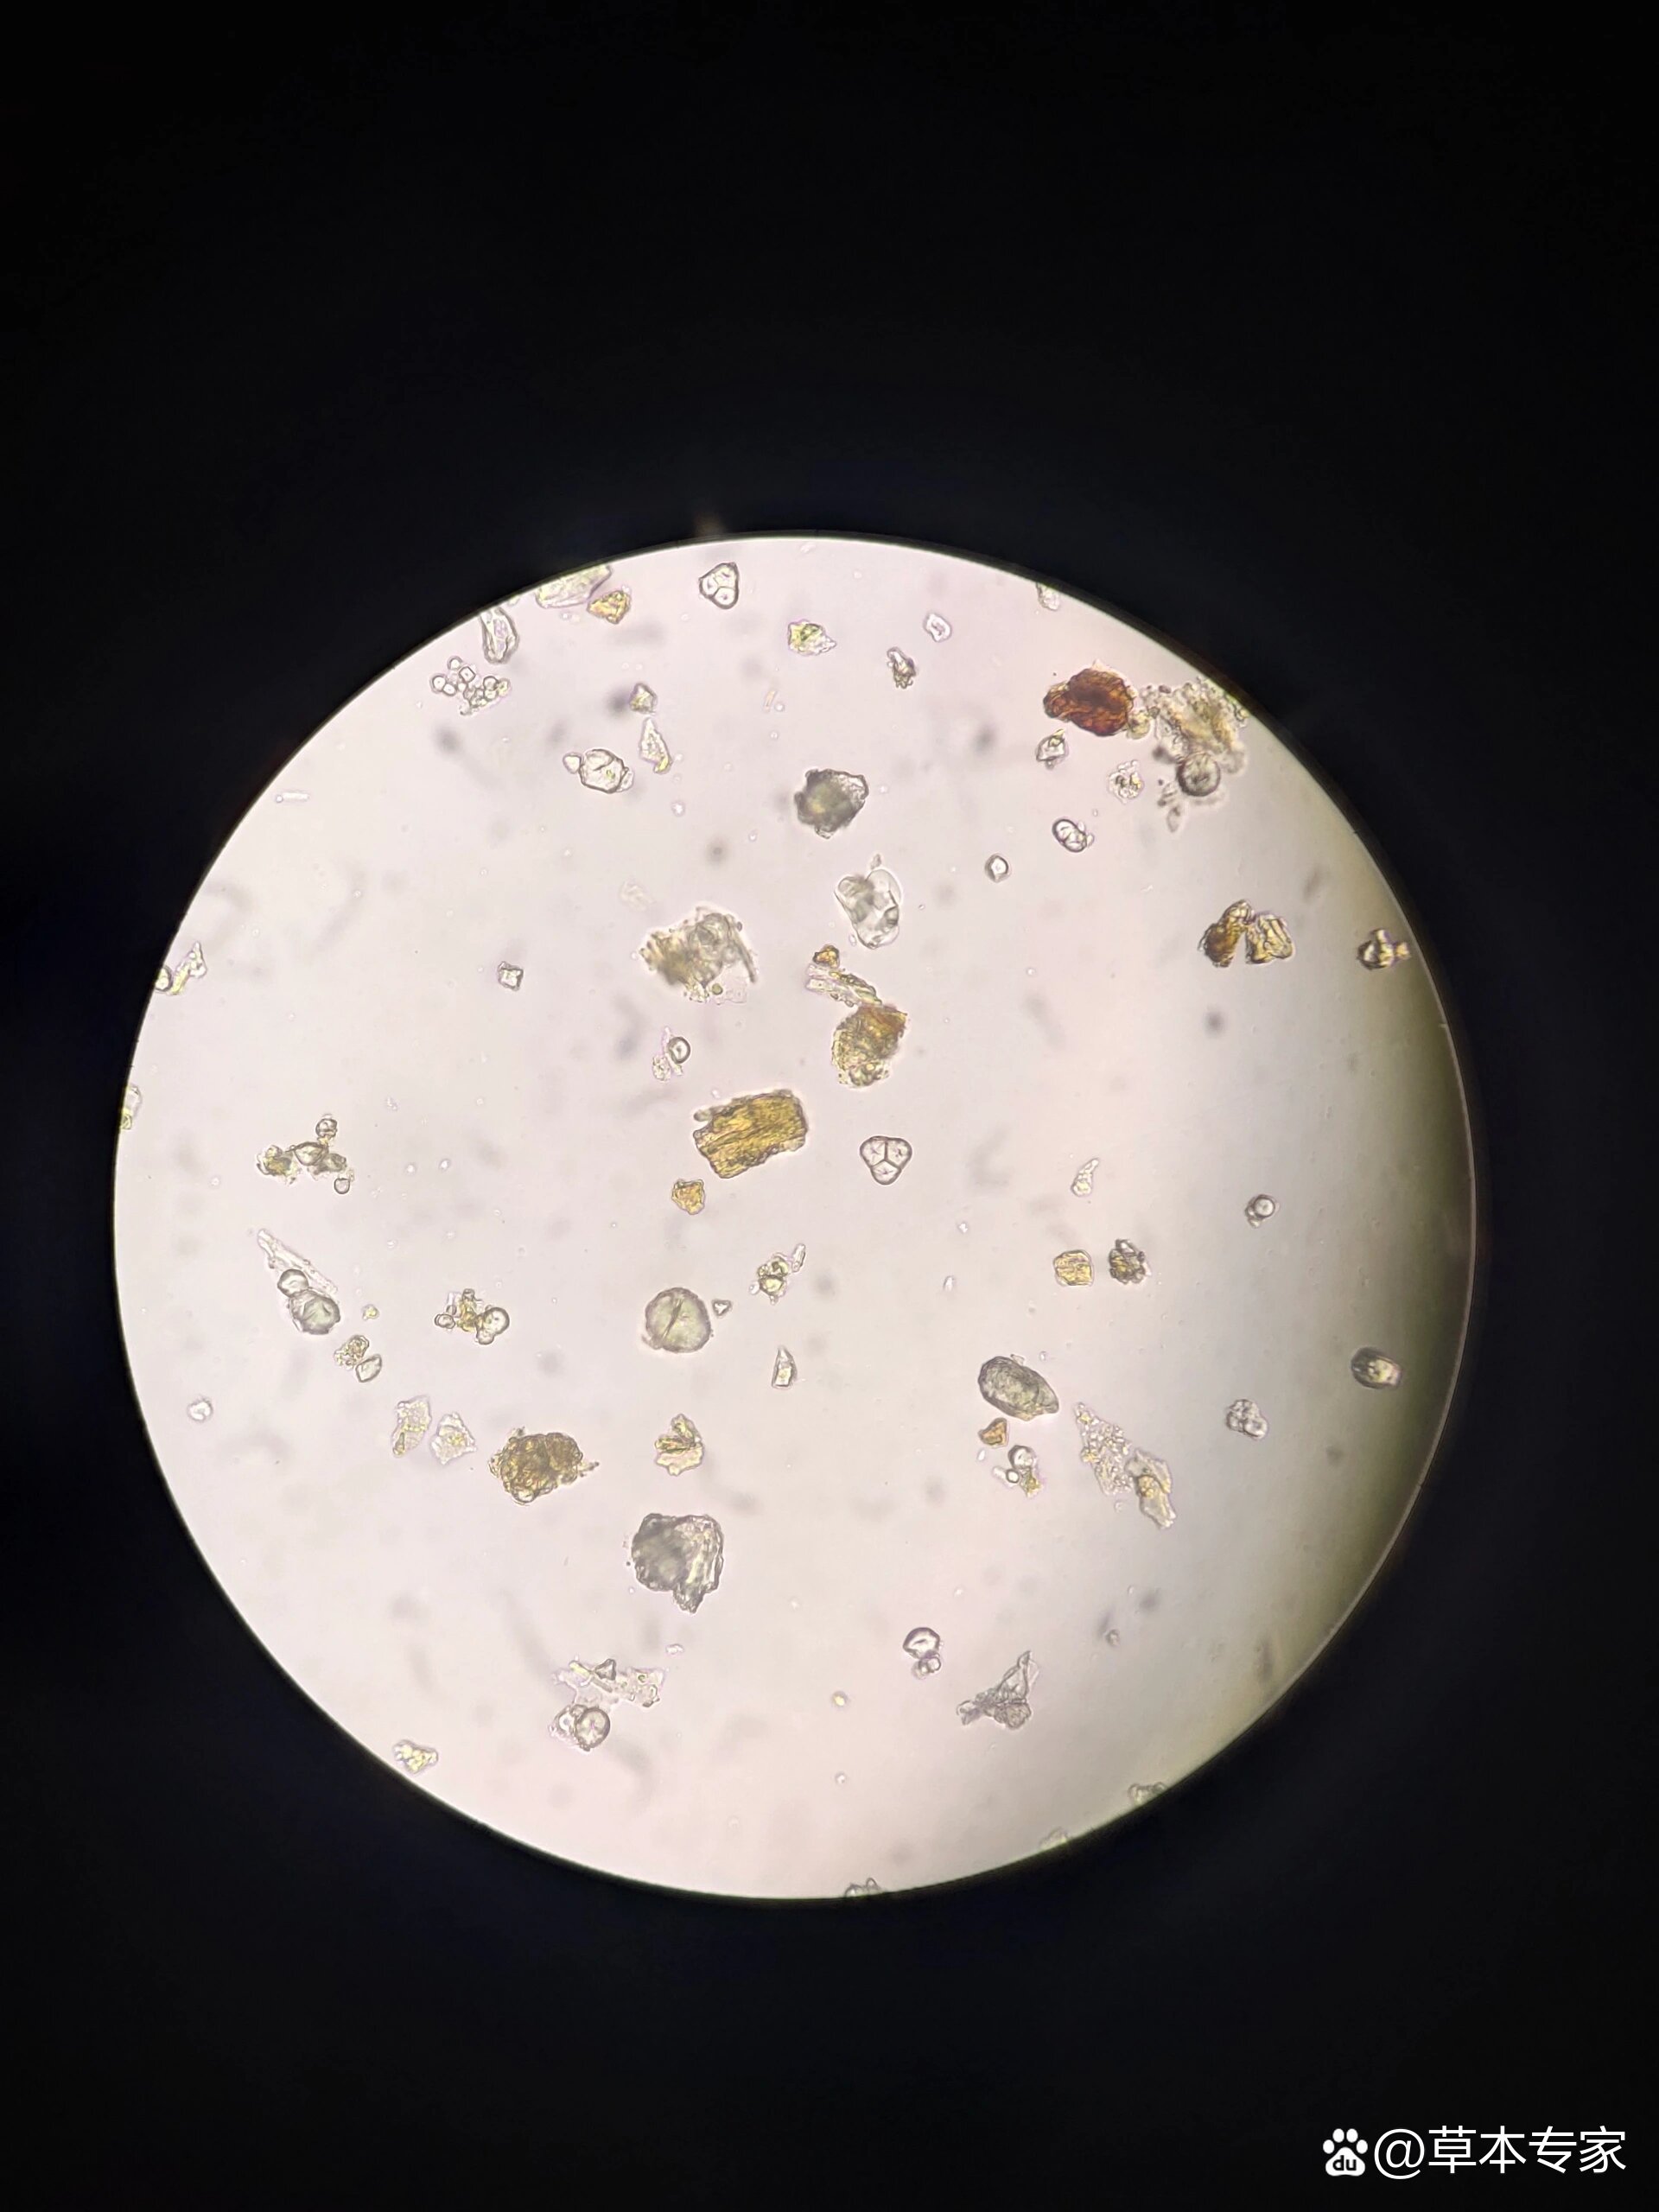

大黄粉末显微图